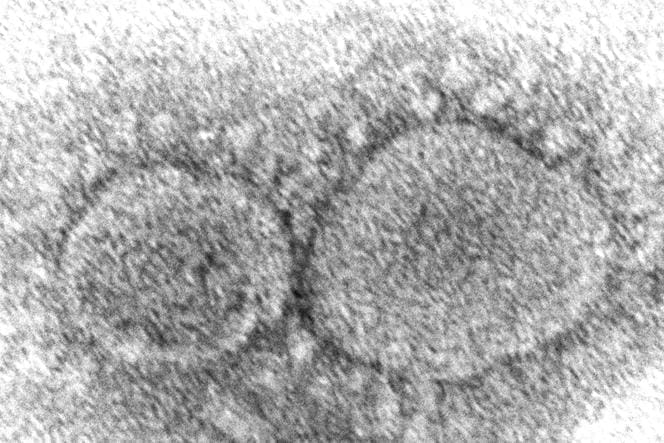

Le 26 décembre 2019, la Chine a révélé l’émergence d’un coronavirus, étroitement lié au SRAS, connu pour avoir causé des ravages en Asie en 2003. Cette nouvelle a déclenché un ensemble d’analyses et d’alertes sanitaires à travers le monde. Cependant, les détails concernant cette souche, son origine et sa propagation sont demeurés flous. Ces incertitudes persistent, éveillant la curiosité des virologues et des journalistes d’investigation.